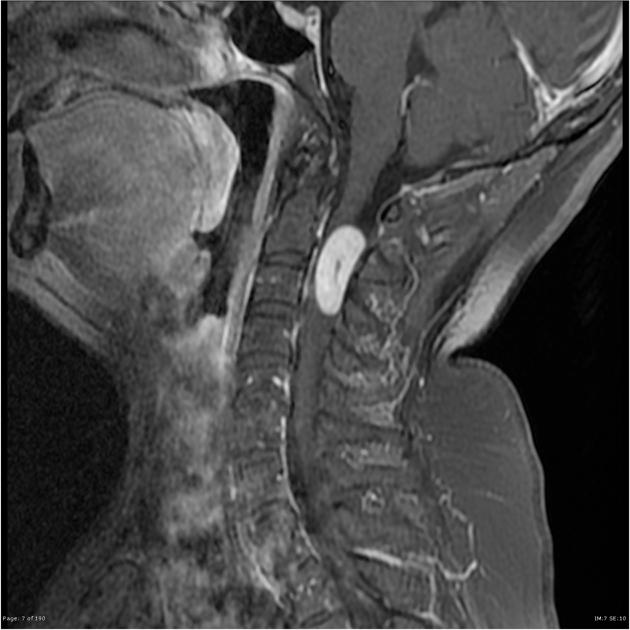

rheumatoid pannus

inflammatory synovial tissue commonly growing in cervical spine around C1-2, can cause neck pain/instability and cord compression